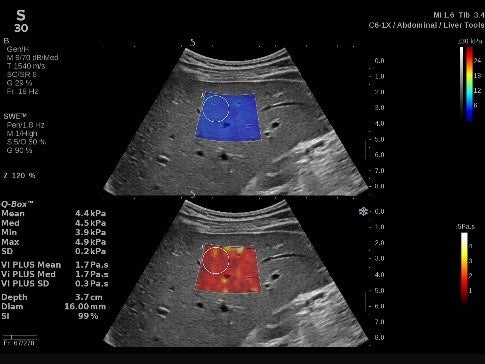

(3)新たに搭載したVi PLUS™イメージング

肝臓組織の粘性の定量化、弾性率のリアルタイム表示、剪断弾性波伝搬速度のディスパージョン評価を可能*にするモードです。

*C6-1Xプローブ、Liver & Abdomenプリセット、Generalプリセット使用時SWE PLUS™イメージングとVi PLUS™イメージングは同時リアルタイムに表示されます。

SWE PLUS™イメージングとVi PLUS™イメージングは同時リアルタイムに表示されます。